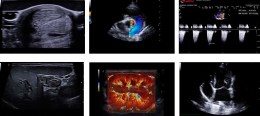

Ультразвуковий ветеринарний сканер MyLab Sigma Vet - портативна ультразвукова система, розроблена Esaote спеціально для ветеринарної медицини. Сканер поєднує мобільність та автономність з якістю зображення, що робить його чудовим інструментом для клініки чи операційної. Система оснащена потужним процесором, сучасним ПЗ з інтелектуальними функціями та підтримує широкий спектр спеціалізованих датчиків.

Висока якість зображення та глибока діагностика

Апаратні та цифрові технології, поєднані з ліцензіями TEI (покращення візуалізації тканин, друга гармоніка), PBI (збереження високої роздільної здатності на великій глибині) та X-View/M-View (зниження артефактів та спекл-шуму), дозволяють отримувати чітке, контрастне зображення, необхідне для точної діагностики технічно складних пацієнтів

Експертні можливості в кардіології та доплерографії

Розширений кардіологічний пакет Cardio включає ліцензії CW/PW/HPRF Допплер, а також спеціалізовані режими, як-от СММ (мультинаправлений анатомічний М-режим) та TVM (картування швидкості тканин) для детального аналізу руху стінок міокарда. Режими X-CFM та X-Flow забезпечують чутливу візуалізацію кровотоку, включаючи низькошвидкісний.